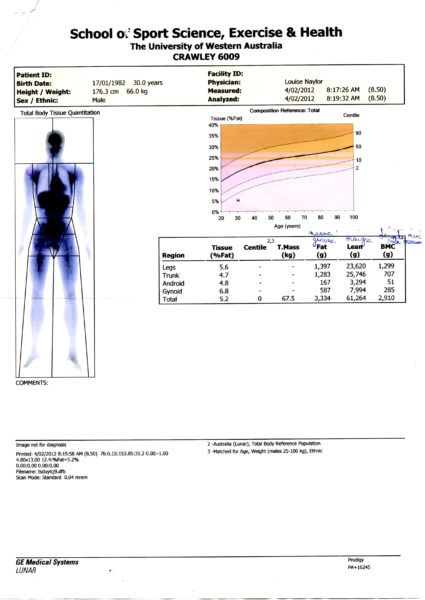

Avec les années d’entraînement, l’augmentation de la charge d’entraînement et une nutrition drastique qui bannissait toute une panoplie de produits de la consommation, je suis arrivé à un taux de masse grasse de 3,2%. On sait dans la littérature scientifique qu’un taux inférieur à 5% n’est pas sain et qu’une mort par maladie notamment cancer est augmentée Cela a été le déclic pour moi. Heureusement pour moi, j’étais à la Faculté des Sciences du Sport à Poitiers. J’ai demandé l’aide à l’une de mes professeurs, Nathalie Boisseau. On a commencé par évaluer de la manière la plus précise ma composition corporelle. Pour se faire, je suis allé à Orléans où se trouvait à l’époque l’un des deux seuls Dexa en France.

Le DEXA, initialement développée dans les années 80 pour la mesure du contenu minéral osseux, s’est imposée comme la méthode de référence pour l’étude de la composition corporelle. Elle consiste à balayer l’ensemble du corps avec un faisceau de rayons X à deux niveaux d’énergie. Le rapport des atténuations de ces deux rayonnements est fonction de la composition de la matière traversée. L’irradiation imposée au patient est faible et similaire à celle correspondant à une radiographie pulmonaire. La calibration est effectuée avec des fantômes artificiels contenant des triglycérides et du calcium. Le DEXA permet de séparer trois compartiments (masse grasse, masse maigre et contenu minéral osseux) par un traitement informatique des mesures physiques. La précision est excellente. le DEXA mesure la valeur du compartiment osseux, négligé jusque-là. Le balayage du corps entier et le traitement d’images permettent une approche régionale (bras, tronc, jambes) des trois compartiments mesurés, impossible à réaliser avec les autres méthodes. J’ai eu l’occasion d’en refaire un en Australie lorsque je m’entraînais avec l’Unviersity Western Australia avant mon accident.

Les résultats obtenus montraient que j’étais trop « sec » pour celui fait en France. On connaissait la conséquence. Il fallait maintenant en comprendre les raisons.

On a donc évalué sur une semaine complète quelles étaient mes dépenses et recettes énergétiques. En clair, je notais et pesais tout ce que je mangeais et buvais sur une semaine complète. De l’autre côté de la balance, je consignais tous mes entraînements et courbes d’analyses de fréquence cardiaque. Nathalie avait calculé à l’époque que je dépensais autour des 7000 calories par jour, mais que mon alimentation malgré les nombreuses collations n’apportaient que 6000 calories. Il a fallu établir un programme nutritionnel adapté à ma pratique. Le DEXA avait également montré que, quand bien même mon contenu minéral osseux était dans la norme, il était dans la limite basse. Ceci est un indice annonciateur d’un surentraînement qui pourrait engendrer une fracture de fatigue. Deux endroits sont analysés par la machine, le col du fémur et le bas du dos.